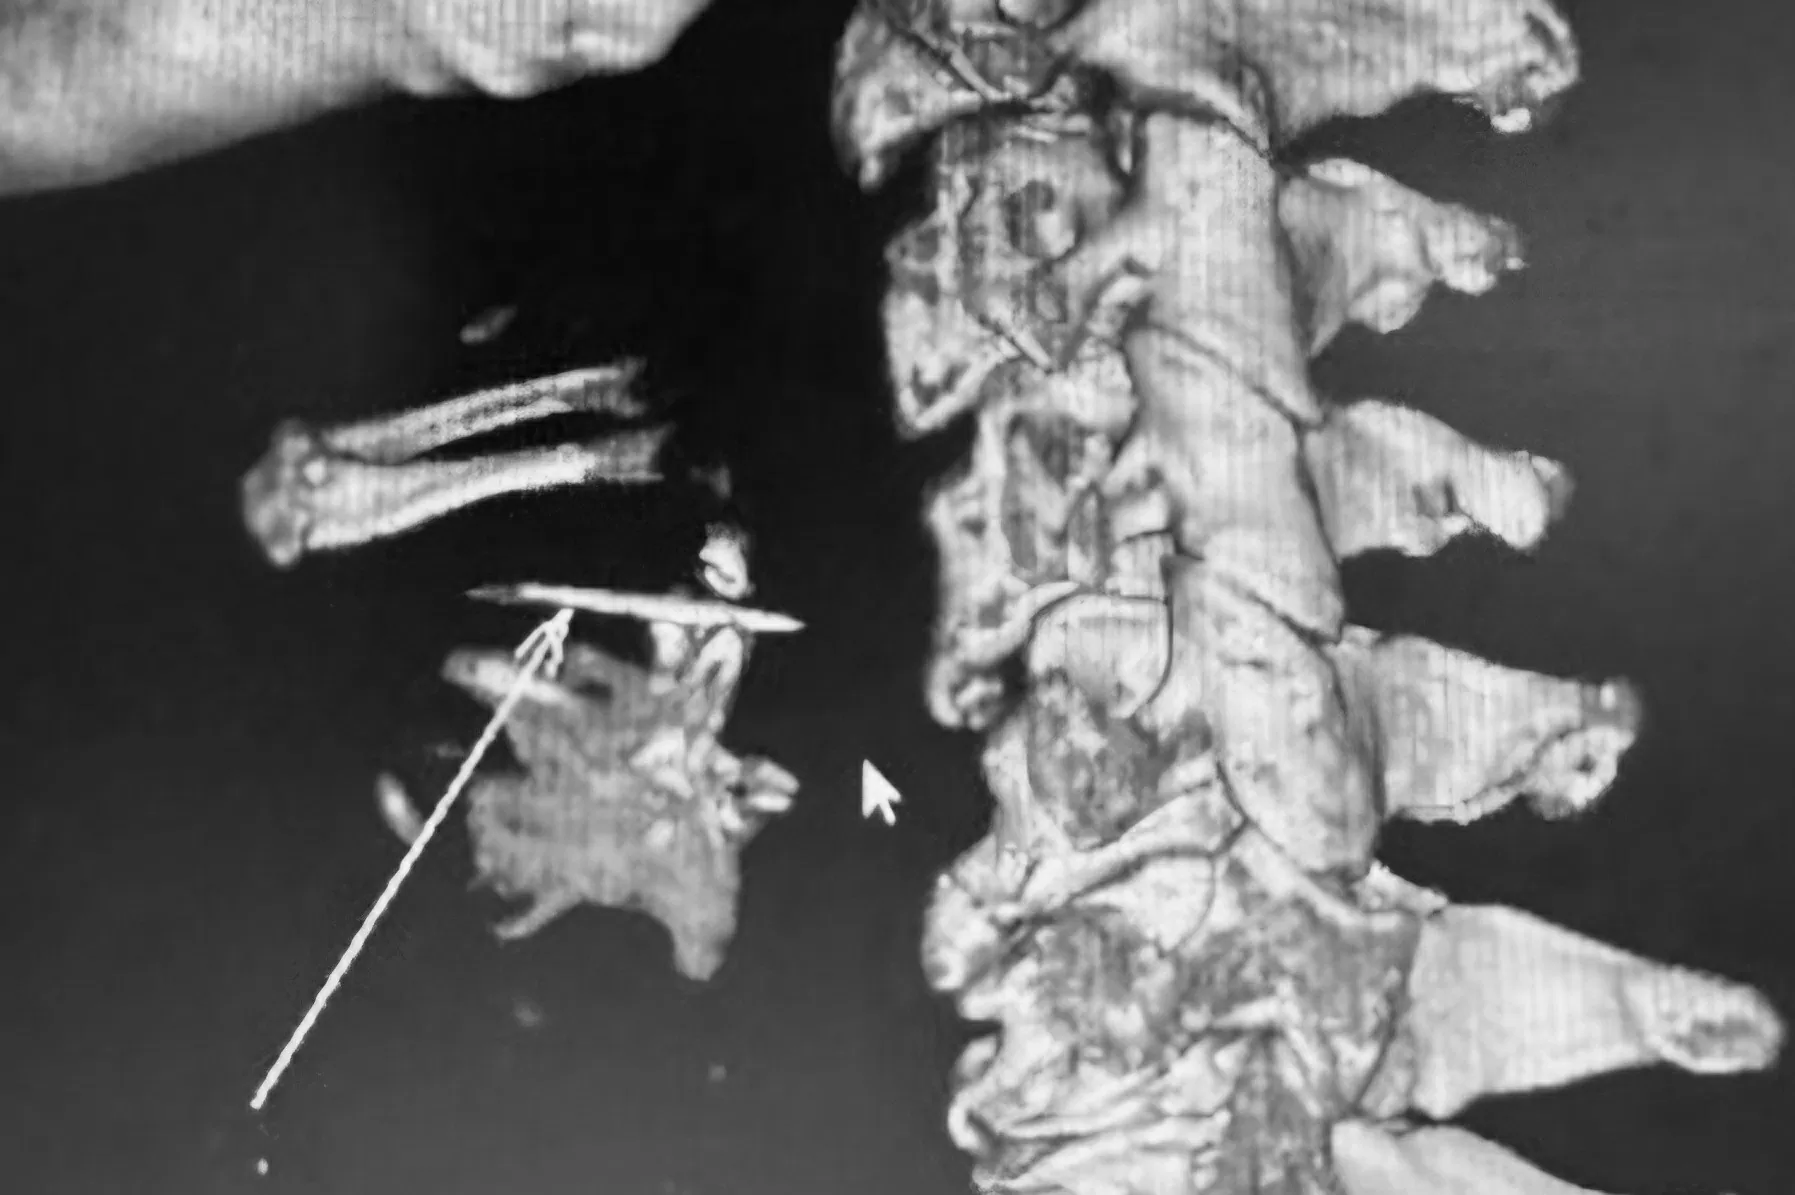

| Hình ảnh dị vật trên phim chụp vi tính sau khi bệnh nhân được các bác sĩ cấp cứu. (Ảnh: BVCC) |

Tại bệnh viện, các bác sĩ chẩn đoán nguyên nhân do hóc xương cá dẫn đến viêm tấy, phù nề hạ họng phải. Nhận định đây là trường hợp hóc dị vật phức tạp, các bác sĩ chỉ định chụp cắt lớp vi tính 64 dãy có dựng hình 3D. Kết quả cho thấy xương cá nằm ở xoang lê bên phải, cạnh thành khí quản, ngang mức đốt sống C4. Đây là vị trí rất nguy hiểm vì dị vật có thể gây viêm nhiễm nặng tại chỗ và toàn thân; tổn thương thành họng, dẫn đến áp xe; tổn thương các mạch máu lớn; chèn ép đường thở, gây ngạt thở và tử vong.